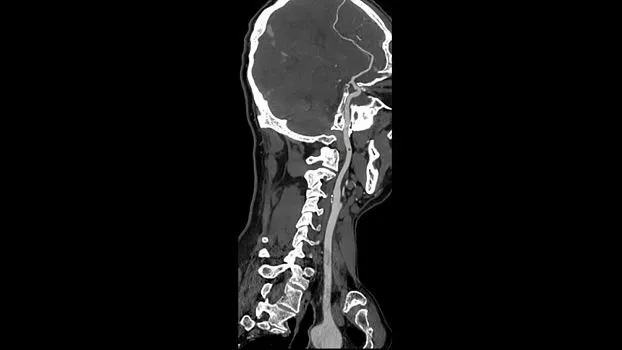

Клинические изображения

Технология TrueFidelity

Revolution Ascend поддерживает технологию TrueFidelity**, которая реконструирует изображения с помощью алгоритмов глубокого обучения. Она обеспечивает глубокую детализацию, естественную текстуру, высокую контрастность и четкость изображений. TrueFidelity генерирует изображения с помощью алгоритмов искусственного интеллекта. Это позволяет, с одной стороны, использовать низкую лучевую нагрузку, как при итеративной реконструкции, а с другой стороны, получать изображения, не уступающие по качеству методу фильтрованных обратных проекций.

В Revolution Ascend сочетаются новая конструкция гентри диаметром 75 см и более низкое расположение стола, что позволяет увеличить площадь внутри туннеля, в пределах которой располагается пациент, на 22% по сравнению со сканерами GE HealthCare предыдущего поколения. Таким образом, пациенты чувствуют себя более комфортно во время КТ-исследований. Благодаря новой конструкции гентри, Revolution Ascend – КТ с самой большой апертурой среди систем с короткой геометрией¹. Это означает, что вы сможете проводить КТ пациентам крупного телосложения, а также пациентам с травмами, которые испытывали бы дискомфорт и не смогли бы свободно двигаться, если бы сканирование проходило в гентри меньшего размера.